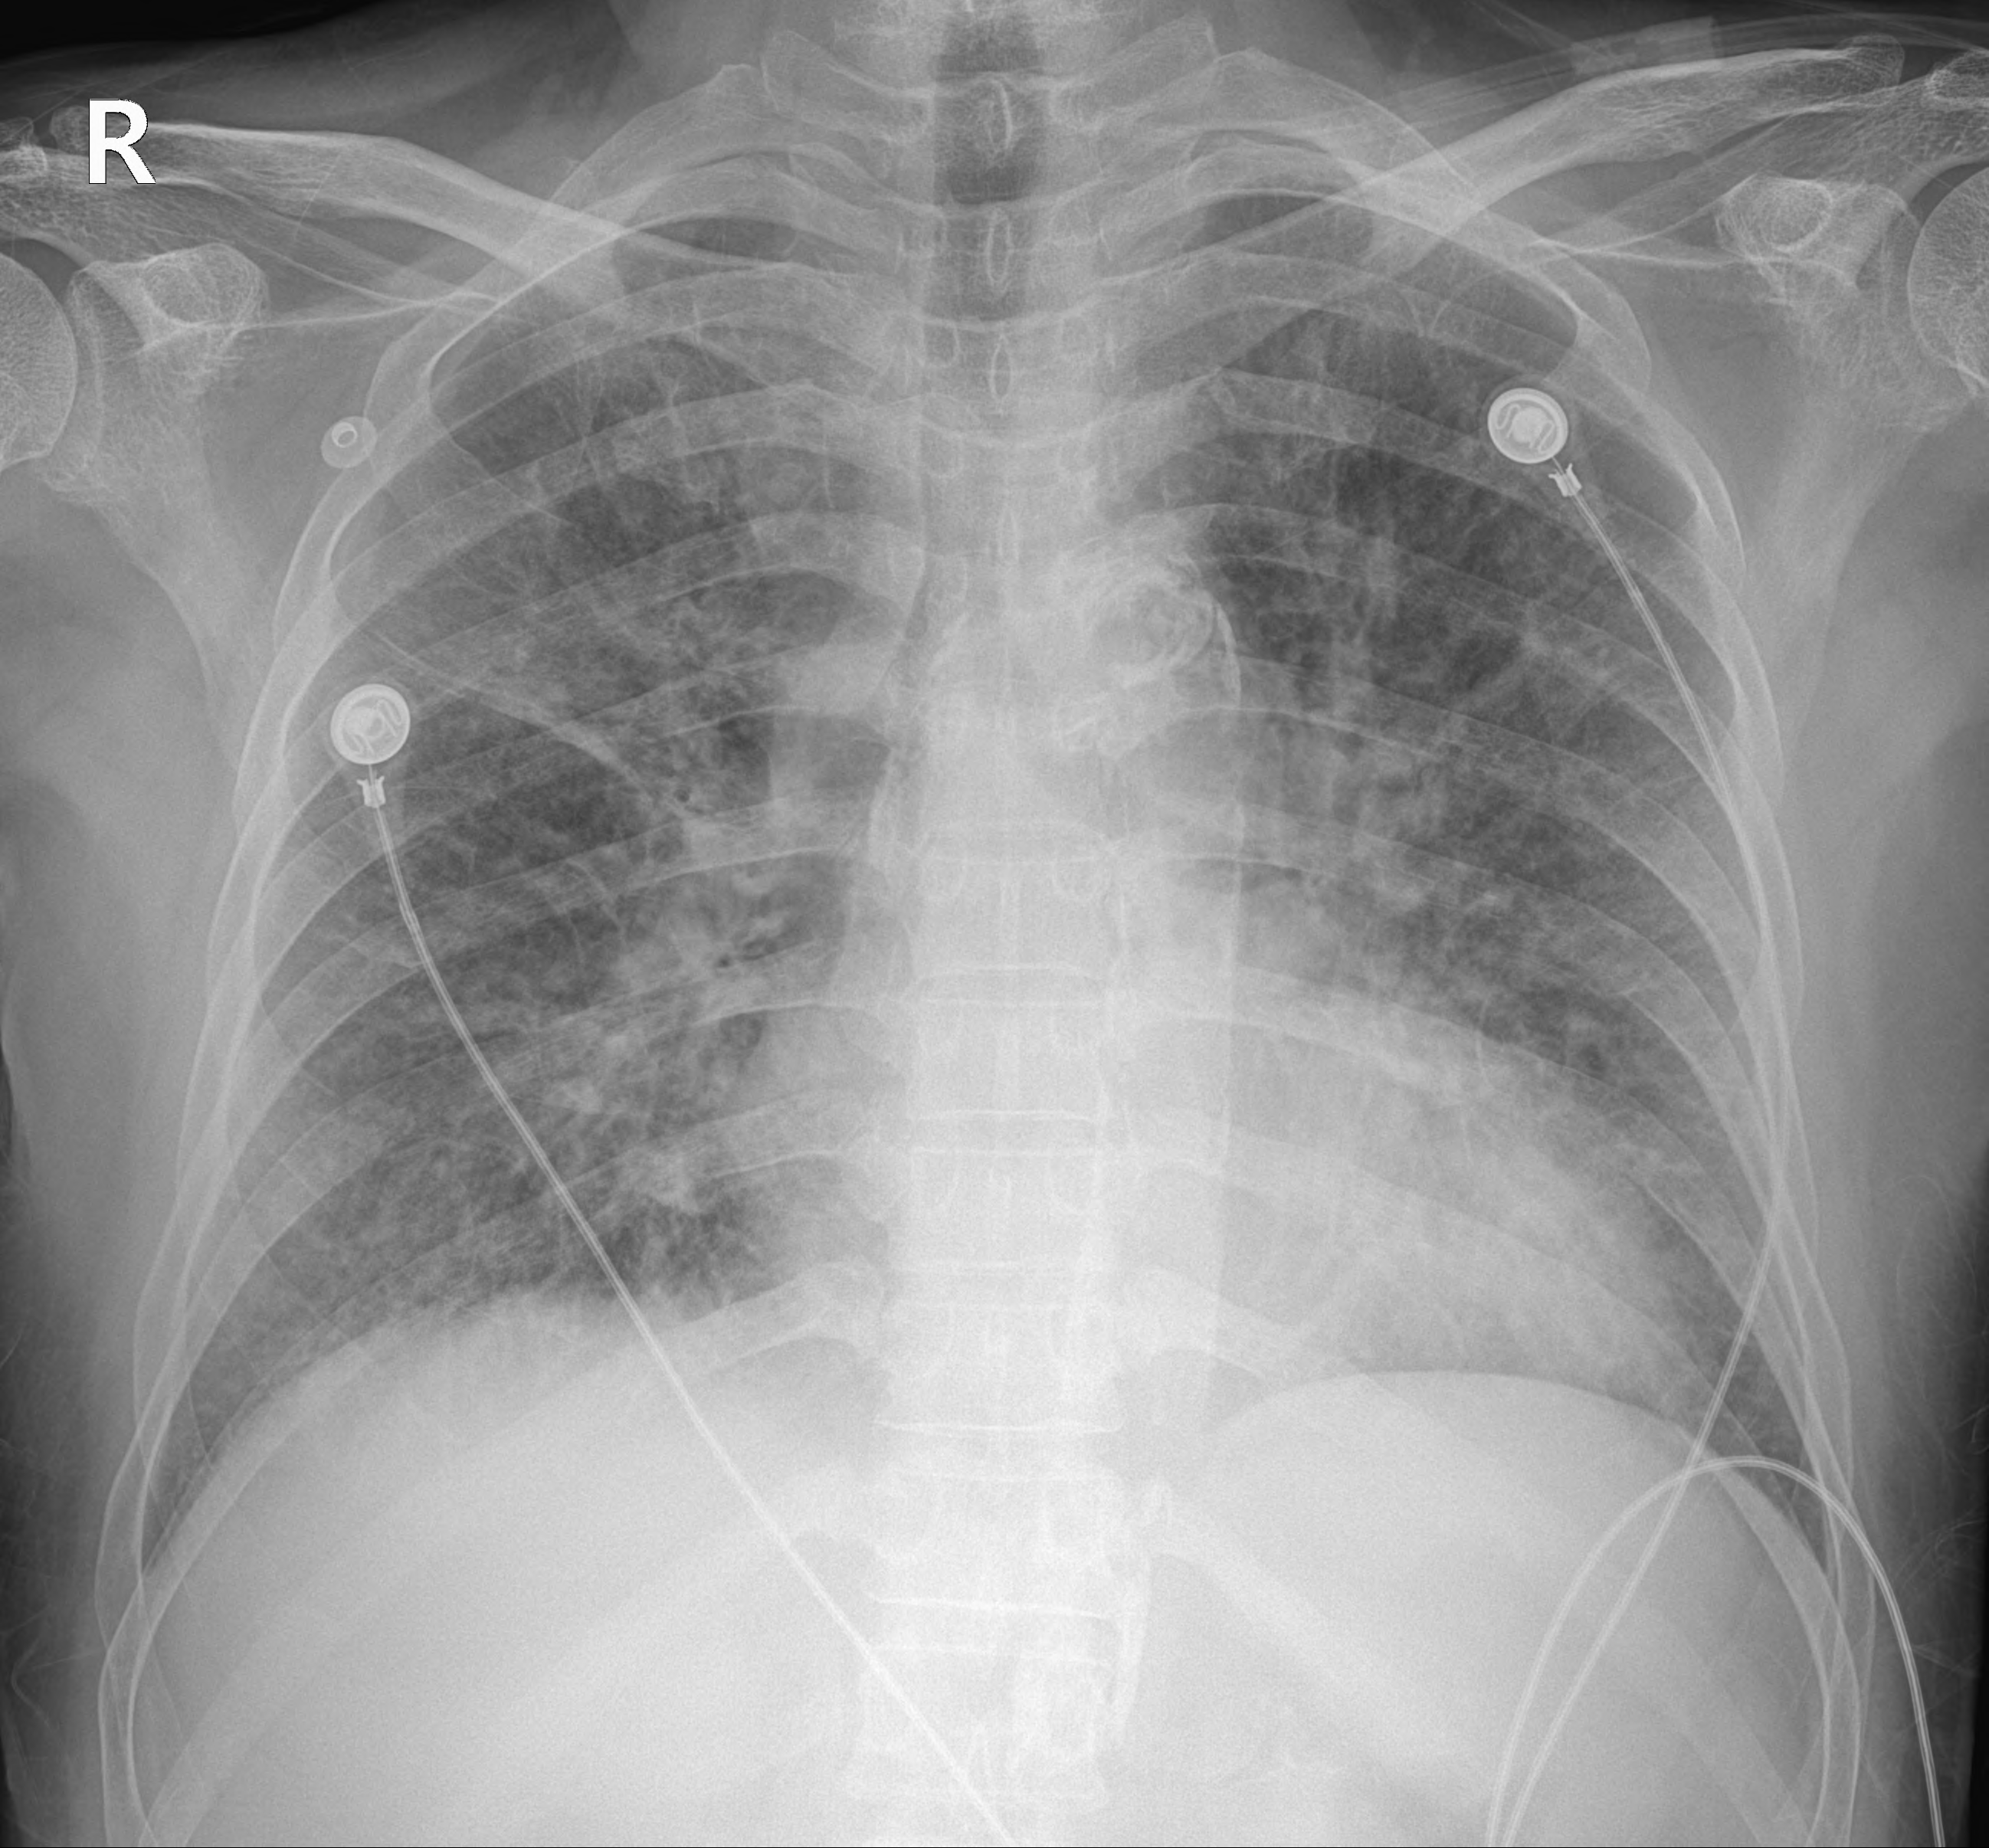

응급실에서 시행한 검사 결과 환자는 폐부종을 동반한 심근경색이 생긴 상태였다.

다행히 환자분이 직업은 있으나, 월급이 적어 지원가능해보였다. 하루이틀 뒤 수술을 받을 수 있지 않을까라는 기대감을 갖고 치료를 받던 도중 갑자기 다시 심근경색이 발생하였다. 연달은 심근경색으로 환자분은 급격히 악화되었고, 혈압이 떨이지면서 호흡곤란도 심해져 기관삽관을 하지 않고는 버티기 어려웠다. 따라서 기관삽관을 하고 다시 관상동맥 조영술을 시행하게 되었다. 관상동맥조영술 결과로 심장 관상동맥중에서도 가장 큰 영향력을 갖는 LAD(left anterior descending coronary artery)가 갑작스럽게 막히면서 발생한 심근경색이 확인되었고, 막혔던 부분을 뚫고 스텐트를 넣어주는 PCI 시술을 하게 되었다.

하지만 몇일 사이 거듭된 심근경색으로 환자분의 심장은 기능을 많이 잃었고, 심초음파상에서는 심장 수축률이 30% 정도로 떨어져 있었다.